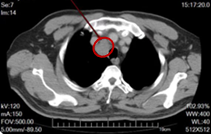

2022-12-02(维持治疗3周期后)复查,颈部、胸部、腹部盆腔平扫及增强CT示:右上气管旁新发淋巴结转移灶,短径约2.8cm。其他结果同前。脑MRI未见异常。

图2.基线及治疗期间复查CT

图3.维持治疗3周期后右上气管旁新发淋巴结转移